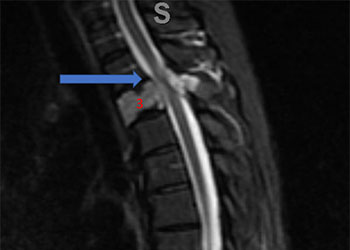

Figure 1. A) Sagittal T2 MRI demonstrates aggressive hyperintense T3 hemangioma involving the body and posterior elements compressing the thoracic spinal cord (arrows) Figure 1. B […]